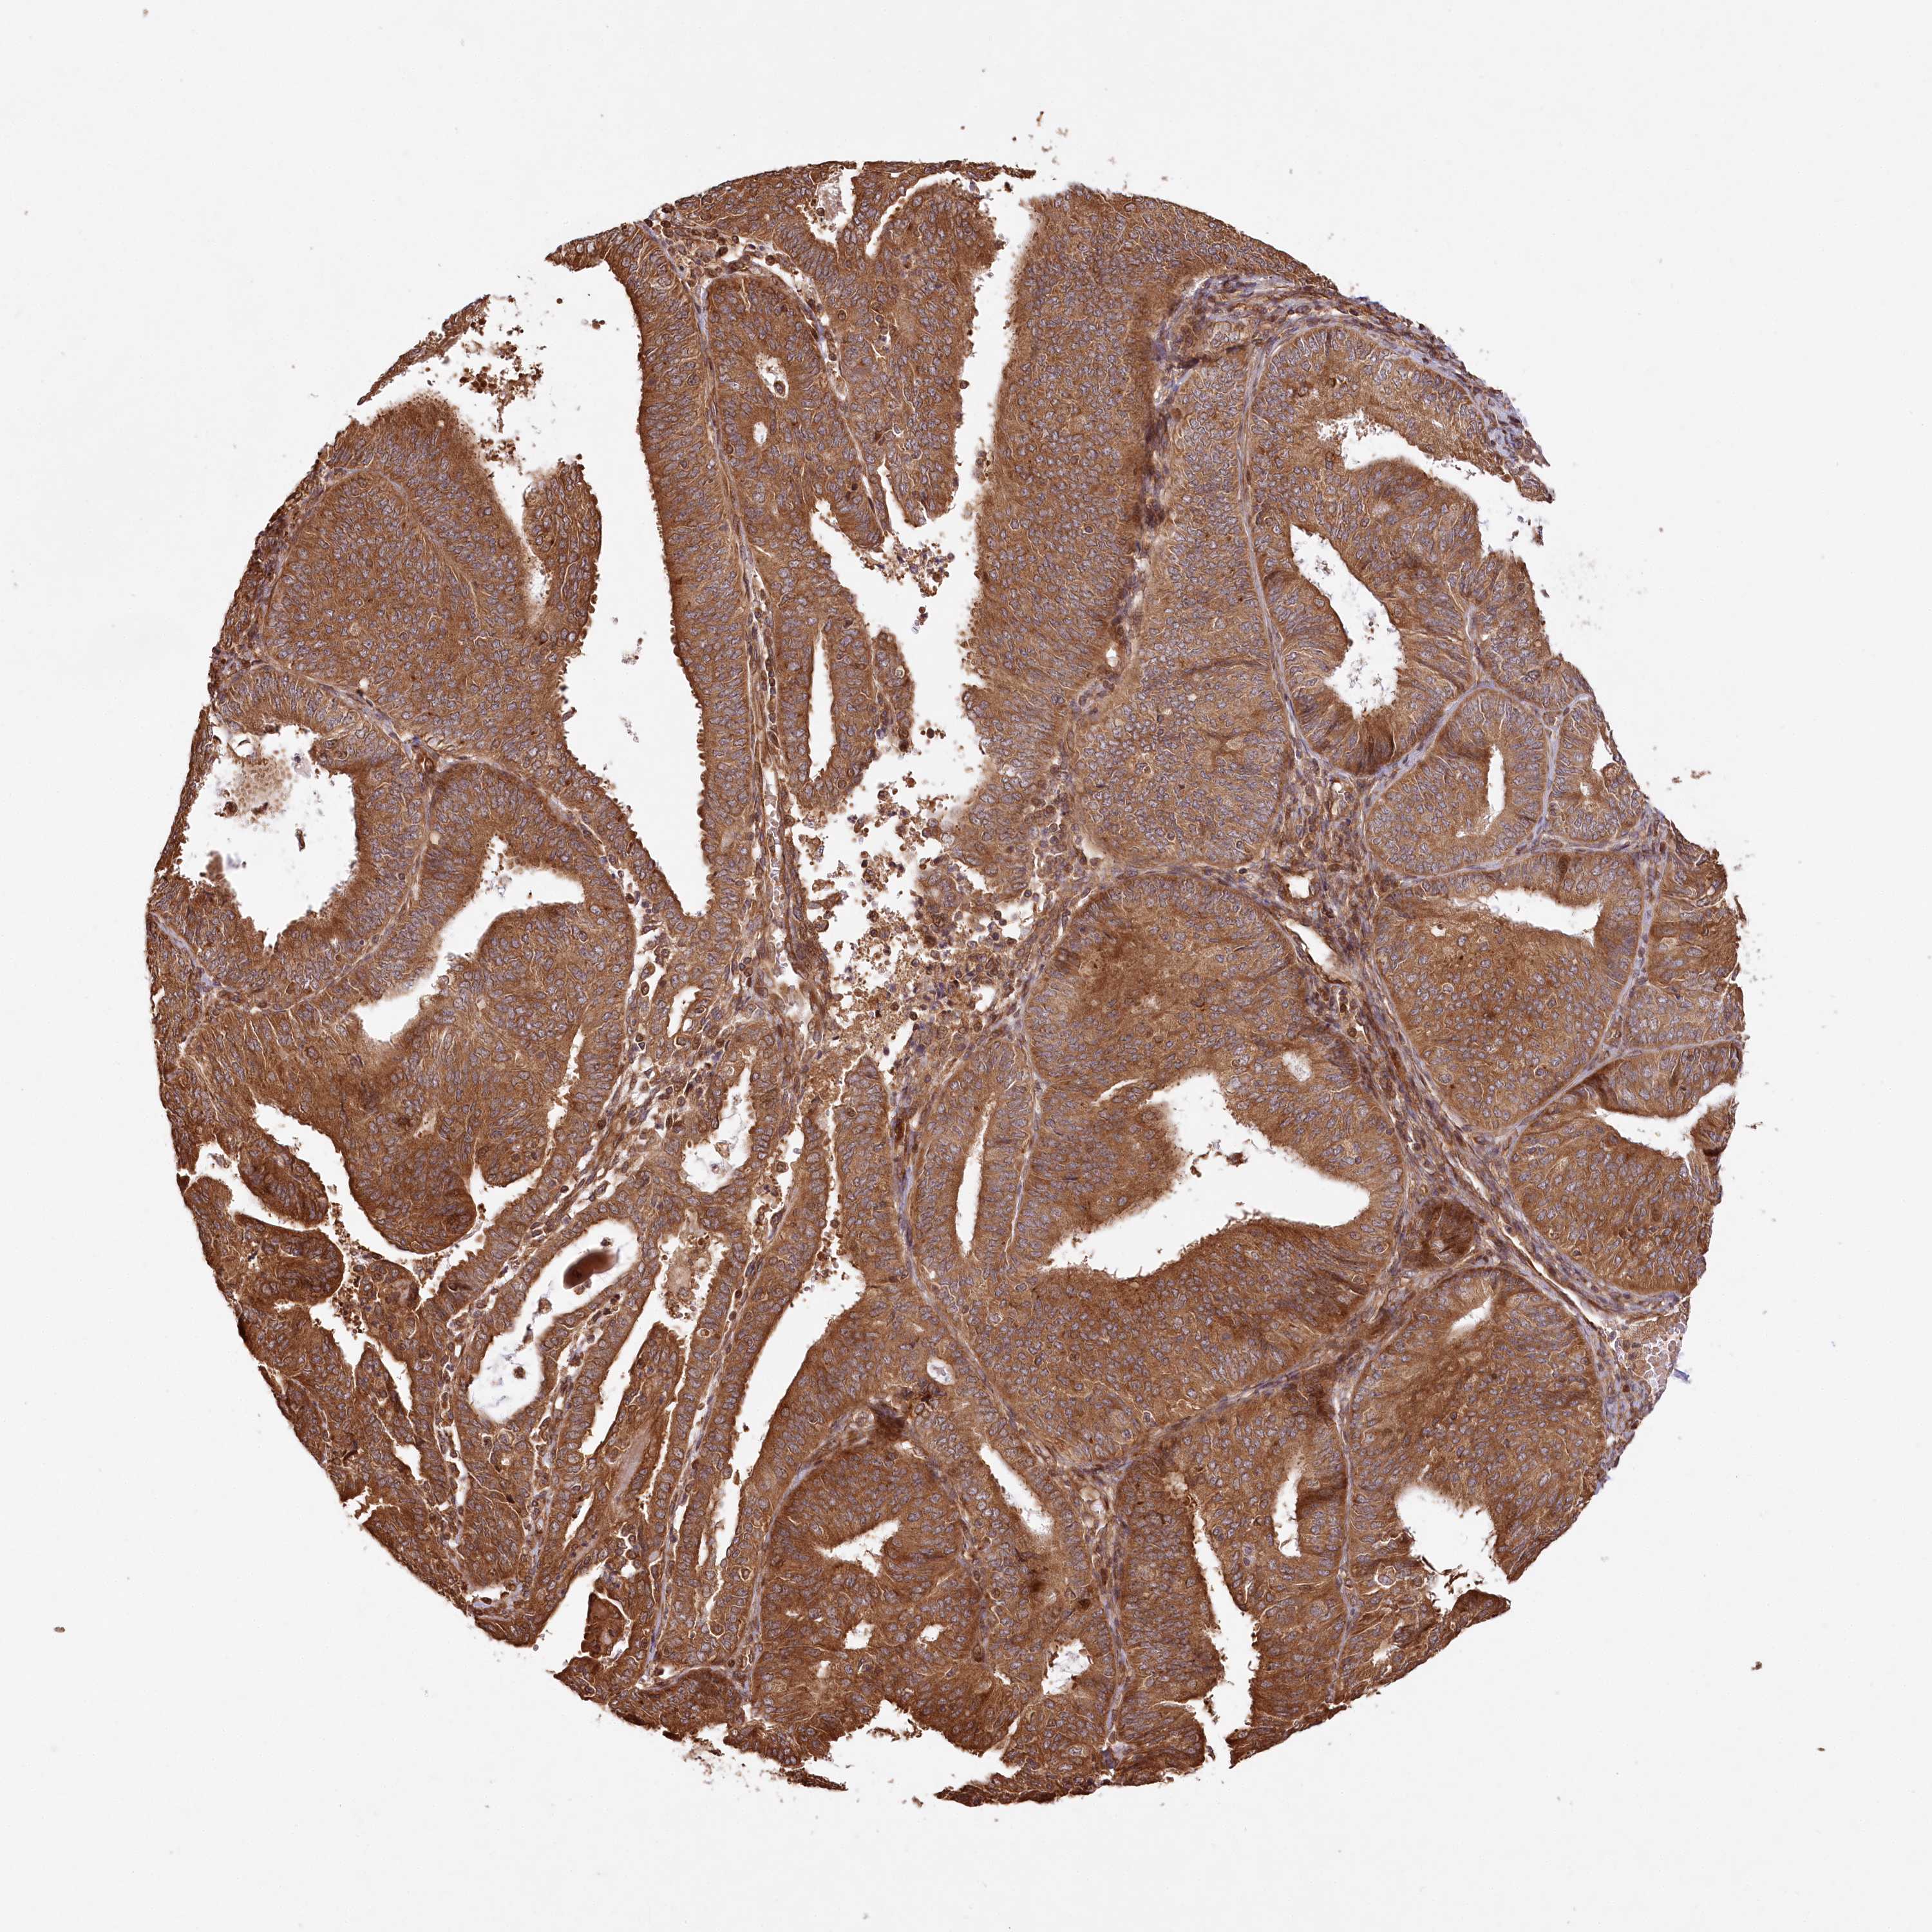

ENDOMETRIAL CANCER - Protein expressioni

A mouse-over function shows sample information and annotation data. Click on an image to view it in a full screen mode. Samples can be filtered based on level of antibody staining by selecting one or several of the following categories: high, medium, low and not detected. The assay and annotation is described here.

Note that samples used for immunohistochemistry by the Human Protein Atlas do not correspond to samples in the TCGA dataset.

Antibody stainingi

Antibody staining in the annotated cell types in the current human tissue is reported as not detected, low, medium, or high, based on conventional immunohistochemistry profiling in selected tissues. This score is based on the combination of the staining intensity and fraction of stained cells.

Each image is clickable and will lead to virtual microscopy that enables deeper exploration of all samples and also displays staining intensity scores, fraction scores and subcellular localization as well as patient and tissue information for each sample.

Antibody HPA032060

Antibody HPA032062

Antibody CAB034116

Staining

High

Medium

Low

Not detected

Intensity

Strong

Moderate

Weak

Negative

Quantity

>75%

75%-25%

<25%

None

Location

Nuclear

Cytoplasmic/membranous

Cytoplasmic/membranous,nuclear

Adenocarcinoma, NOS

Adenocarcinoma, metastatic, NOS